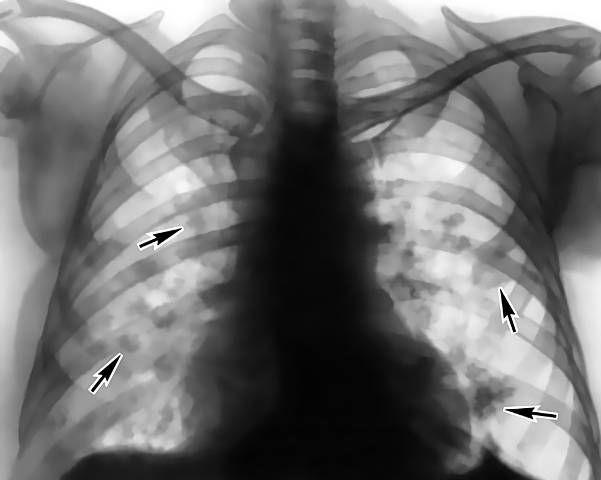

Синдром Леффлера — одна из разновидностей самостоятельных форм эозинофилии. Причины его точно не установлены, вероятно, ими могут быть паразиты, аллергены из воздуха, лекарства. Синдром протекает благоприятно, жалобы или отсутствуют, или больной отмечает кашель, небольшое повышение температуры.

В легких при синдроме Леффлера образуются скопления эозинофилов, которые разрешаются сами собой, не оставляя последствий, поэтому патология заканчивается полным выздоровлением. При выслушивании в легких могут быть выявлены хрипы. В общем анализе крови на фоне множественных эозинофильных инфильтратов в легких, выявляемых при рентгенографии, появляется лейкоцитоз и эозинофилия, иногда достигающая 60-70%. Рентгенологическая картина поражения легочной ткани сохраняется до месяца.

В странах с жарким климатом (Индия, Африканский континент) встречается так называемая тропическая эозинофилия, при которой также в легких появляются инфильтраты, в крови нарастает число лейкоцитов и эозинофилов. Предполагается инфекционная природа патологии. Течение тропической эозинофилии — хроническое с рецидивами, но возможно спонтанное излечение.

При легочной локализации эозинофильных инфильтратов эти клетки обнаруживаются не только в периферической крови, но и в выделениях из дыхательных путей. Эозинофилия мокроты и слизи из полости носа характерна для синдрома Леффлера, тропической эозинофилии, бронхиальной астмы, аллергических ринитов, сенной лихорадки.